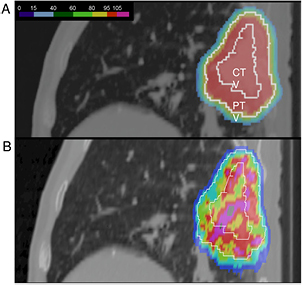

Standard image High-resolution imageFigure 6. The interplay between pencil beam scanning and organ motion jeopardizes the dose distribution. (A) A lung tumor treated with beam scanning assuming no motion. A uniform dose is delivered to the clinical (CTV) and planning (PTV) target volumes. (B) the actual dose distribution caused by patient's breathing. Image courtesy of Prof Christoph Bert, University of Erlangen, Germany.

Download figure: